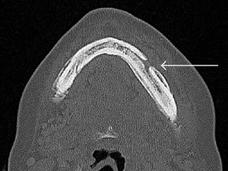

Los problemas de mandíbula relacionados con los medicamentos para tratar enfermedades de los huesos son más comunes de lo que se pensaba

Se pensaba que la osteonecrosis de la mandíbula era un efecto secundario poco común de medicamentos como el denosumab (Xgeva), que disminuyen los problemas óseos cuando el cáncer se diseminó a los huesos. Sin embargo, en un estudio nuevo se descubrió que este doloroso efecto secundario es más común de lo que se creía.